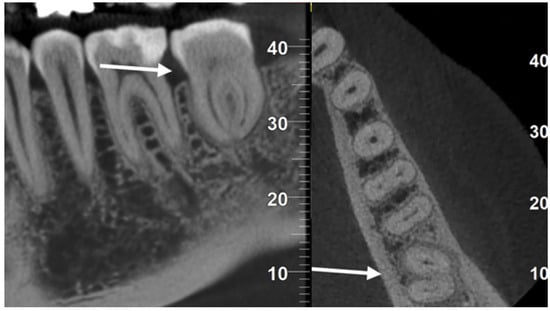

A 42-year-old woman presented to our attention with slight pain in tooth 3.7. The clinical examination revealed a mesial cavity developing deeply under the gingiva, compatible with root resorption. This diagnosis was confirmed by X-ray (Figure 1A) and Cone Beam Computerized Tomography (CBCT). The gum was healthy, and thermal vitality tests testified to the vitality of the affected tooth.

Immediately before the procedure, the patient rinsed with Chlorhexidine 0.3% mouthwash for one minute, and the lips and perioral tissues were disinfected with a povidone-iodine solution. The anesthetic solution with 4% articaine with epinephrine (1:100,000) was delivered locally through an inferior alveolar nerve block and buccal infiltration. The surgery was performed flapless: tooth 3.7 was extracted through a magneto-dynamic device (Magnetic Mallet, Osseotouch, Varese, Italy). After 3.7 extraction and before 3.8 extraction, the recipient socket was prepared with the surgical guides using a specific guided-surgery implant drill kit (Anyridge, Megagen, Seoul, Republic of Korea). Subsequently, the CARP model of tooth 3.8 was inserted in the recipient socket to check the efficacy of the guided surgical protocol. Tooth 3.8 was extracted using forceps, taking care not to injure the PDL; the forces applied were slow and progressive to tear the collagen ligament fibers gently. The donor tooth was immediately inserted into the recipient site as soon as it was extracted, so the extra-alveolar time was approximately one second. No root surface modifications were performed on the donor tooth before the insertion in the socket. The transplanted tooth was then fixed with suspended sutures and a passive flexible wire bonded with a composite (Figure 1B and Figure 2D). An occlusal adjustment was necessary to reduce the occlusal forces.

In this case, given the speed with which the transplantation was performed (approximately 1–2 s of extra-alveolar time), it was decided not to perform the endodontic treatment and to monitor the healing process in order to detect and manage any potential complications like infection, resorption, or ankylosis: clinical and radiograph controls at 2 weeks and 1, 3, 6, 12 (Figure 1C), 24, and 36 months (Figure 1D) showed a perfectly healed tooth.

Figure 1. (A) X-ray showing the cervical root resorption of tooth 3.7; (B) X-ray showing the transplantation of 3.8 in 3.7 position immediately after the surgery; (C) X-ray showing the healing at 1-year follow-up; (D) X-ray at 3-year follow-up.